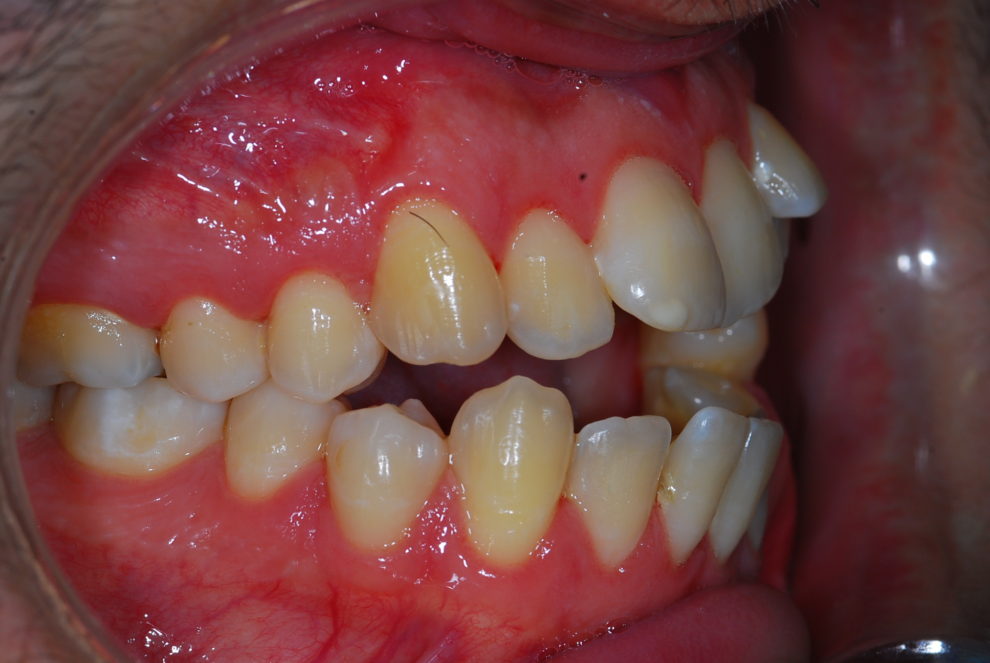

Ortodoncia + Mordida abierta

Nuestro paciente Manuel Vergara Gil acudió a nuestra clínica, y se le hizo una Ortodoncia.